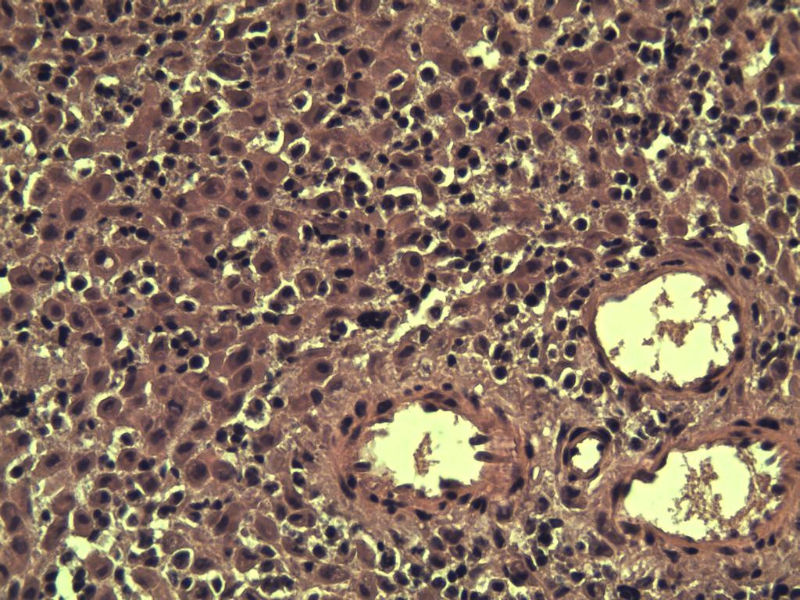

这是另外一个 40岁 经期延长 流血量增多 半年 这是蜕膜样变吧 有什么意义吗? 要报告不?